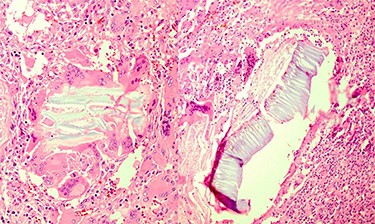

Multinucleated foreign body-type giant cells and inflammatory cells surrounding the vegetable fibers.

Pathology report

Portions of the gastric wall with acute and chronic inflammation were received. Fat necrosis, foreign body-type giant cells, granulomatous formation and fibroblastic proliferation in serosal and perigastric fat were observed, which had infiltrated submucosa in some areas and were attached to the liver tissue (vegetable fibers component?).

Perigastric fat tissue also shows acute and chronic inflammation, fat necrosis and foreign body-type granulomatous formation.

Omentum shows focal foreign body-type granulomatous formation (Fig. 3).

For our patient, after endoscopy and CT scan, EUS was proposed as the final pre-surgical diagnosis, and the report suggested GIST to be the pathology of the tumor. The patient denied any prior similar pain in the past and was transferred to the operating room as a case of GIST. In the operating room, a mass-like lesion was observed and removed. However, it was the pathology report that made this case interesting enough to be included as a case report. The report came out as vegetable fibers component inside the received tissue. Our suspicions are that after the peptic ulcer formed a perforation, food material exited the GI tract and grew to be a vegetable fiber component.